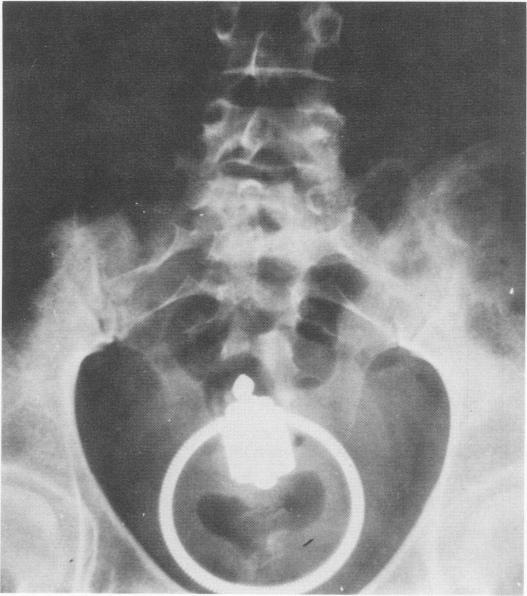

A series comprised of 28 patients (five with perforations of the recto-sigmoid colon and 23 with lodged rectal foreign bodies) is presented. The symptomatology, physical, laboratory and x-ray findings are described. Methods of management are discussed, with emphasis on the operative management of perforations and the conservative approach to retained foreign bodies. It is felt that these protocols will be useful to physicians who see this practice less frequently. X-rays of two more unusual cases are depicted. A thorough review of the literature is also presented. This is the largest reported series of patients with retained rectal foreign bodies and/or perforations. The series includes two female patients, a heretofore unreported occurrence.

本文报告了一组28例患者(5例直肠乙状结肠穿孔,23例直肠内有异物存留)。描述了其症状、体格检查、实验室及X线检查结果。讨论了治疗方法,重点是穿孔的手术治疗及对存留异物的保守处理方法。认为这些方案对较少遇到此类病例的医生会有所帮助。展示了另外两例较特殊病例的X线片。还对文献进行了全面综述。这是所报道的直肠内有异物存留和/或穿孔患者数量最多的一组病例。该组包括两名女性患者,这在此前未曾报道过。